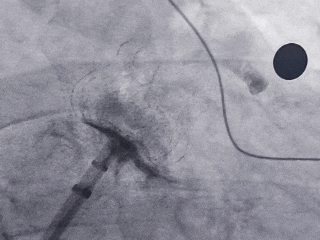

术中操作

鞘管定位

展开过程